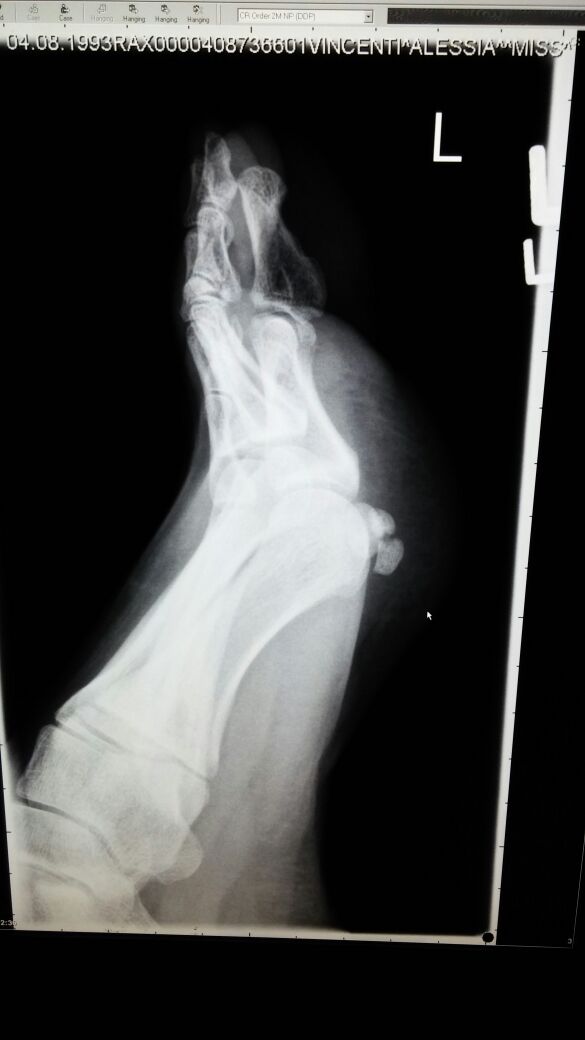

Sono una ragazza di 22 anni. 2 settimane fa ho riscontrato un problema sotto la pianta del piede SX..mi sono alzata una mattina con il piede gonfio. Mentre camminavo mi faceva male. Dopo 3 giorni ho notato che il dolore continuava, sono andata a farmi i raggi. Mi hanno riscontrato un infiammazione dei tessuti molli con successiva visita di uno specialista. In allegato i raggi X.

tmp_29220-IMG-20150202-WA0013-842101486.jpg

[ 52.05 KiB | Osservato 4472 volte ]

dalla sua breve descrizione sembrerebbe trattarsi di una fascite plantare.